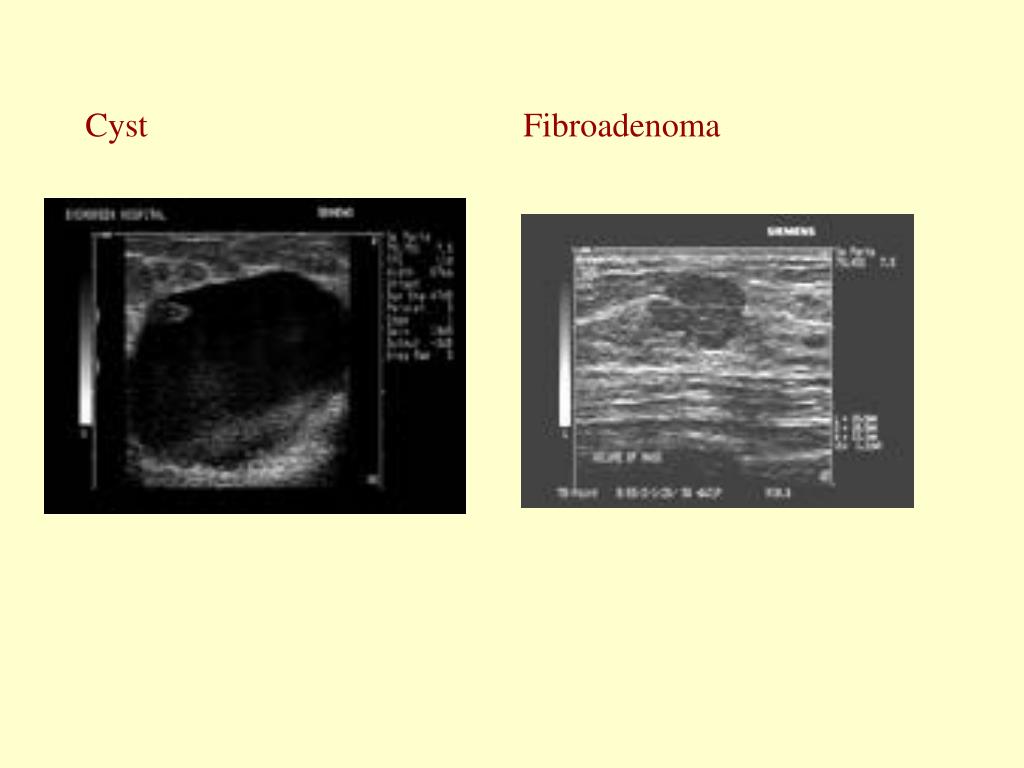

11. Cyst Fibroadenoma

9. Diagnostics • Ultrasound • Useful in the young • Useful in pregnant women • Delineates solid vs cystic • MRI • Possibly the future of breast diagnostics, not there yet, limitations with biopsy

14. Benign, con’t • Fibroadenoma • Very common in young women • Freely mobile and smooth • Characteristic u/s appearance • Half of adenomas resolve if <3cm over 5yrs • Large adenomas should be biopsied to exclude rare phylloides tumor

15. Benign, con’t • Cysts • Due to relative excess estrogen, usually in 4-5th decades • Fluctuate with menses • Aspirate, if bloody then excise, send fluid for path the first time